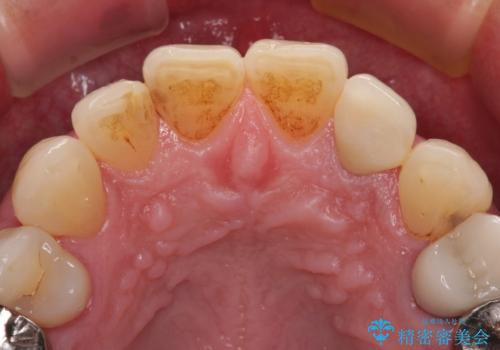

根管治療の土台のまま放置してしまった前歯 オールセラミッククラウンによる補綴治療

- 前歯の根管治療の際に、一時的に見た目を回復したままの状態で放置してしまったとのことで来院された患者様です。

土台の状態は良好であったため、仮歯に置き換えた上でオールセラミッククラウンにて補綴治療を行うこととしました。